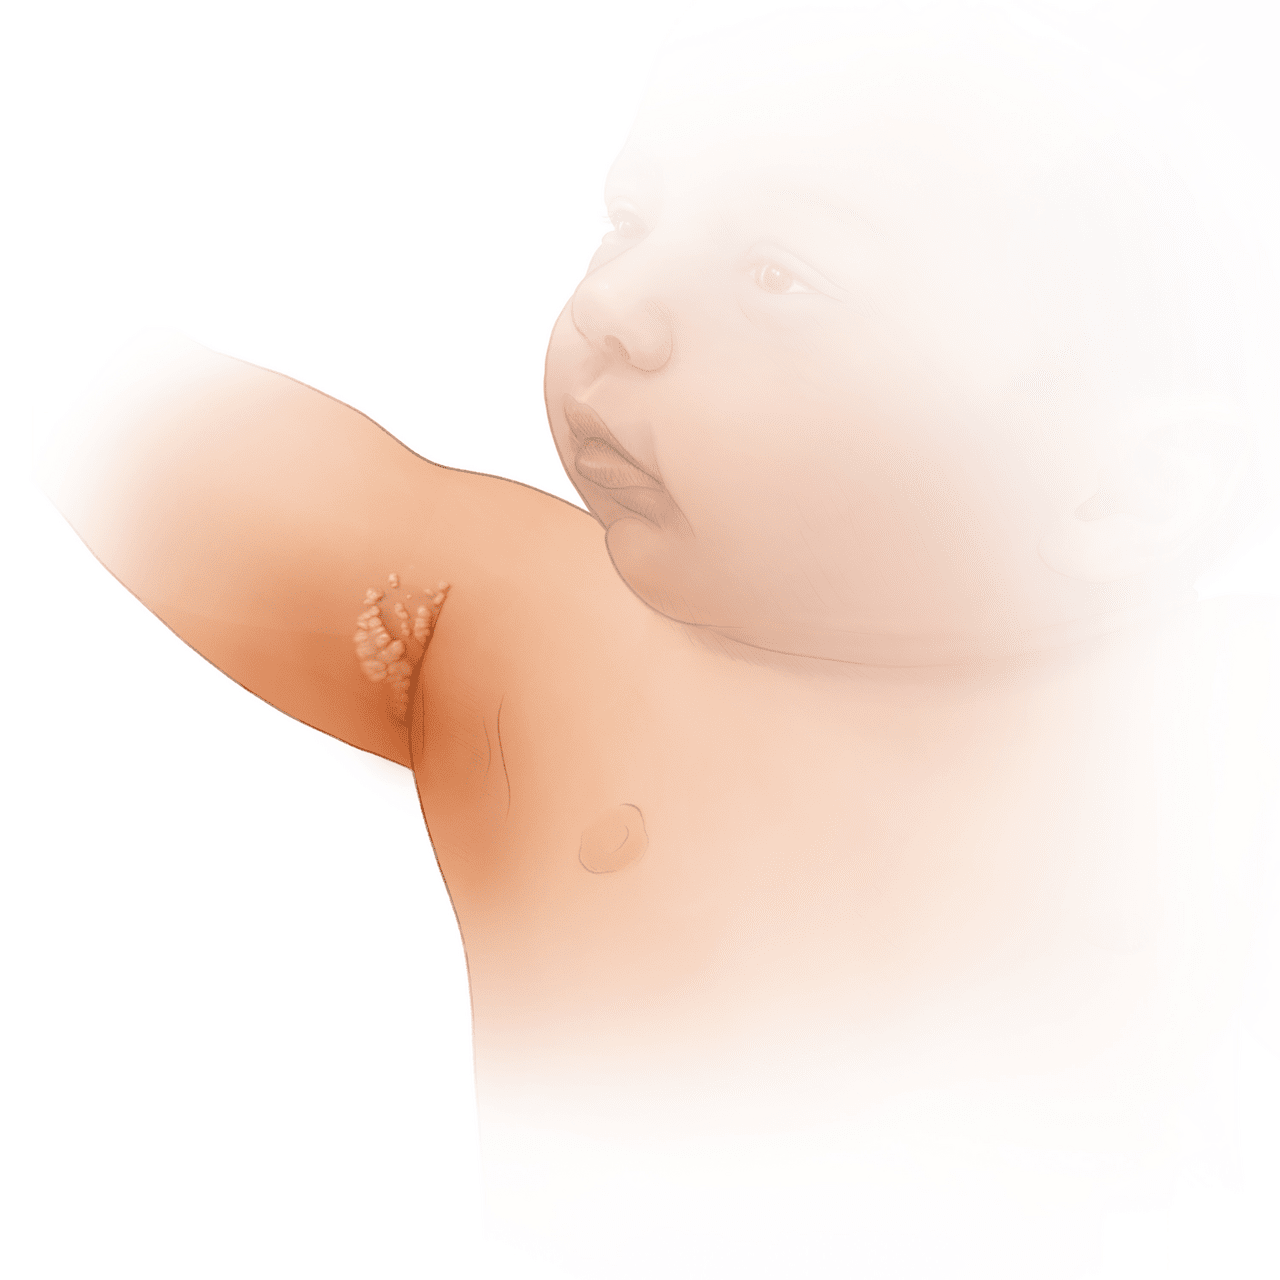

Condylomata lata

Condylomata lata are painless, moist, plaque-like, that moist often develop in warm and moist regions of the body (e.g., inner thighs, perianal, axillae, and skin folds). These lesions are typically teeming with spirochetes.

Details

This photographs show velvety plaques in the perianal region in a newborn with congenital syphilis.

Figure 3. Condylomata Lata in a Newborn with Congenital Syphilis